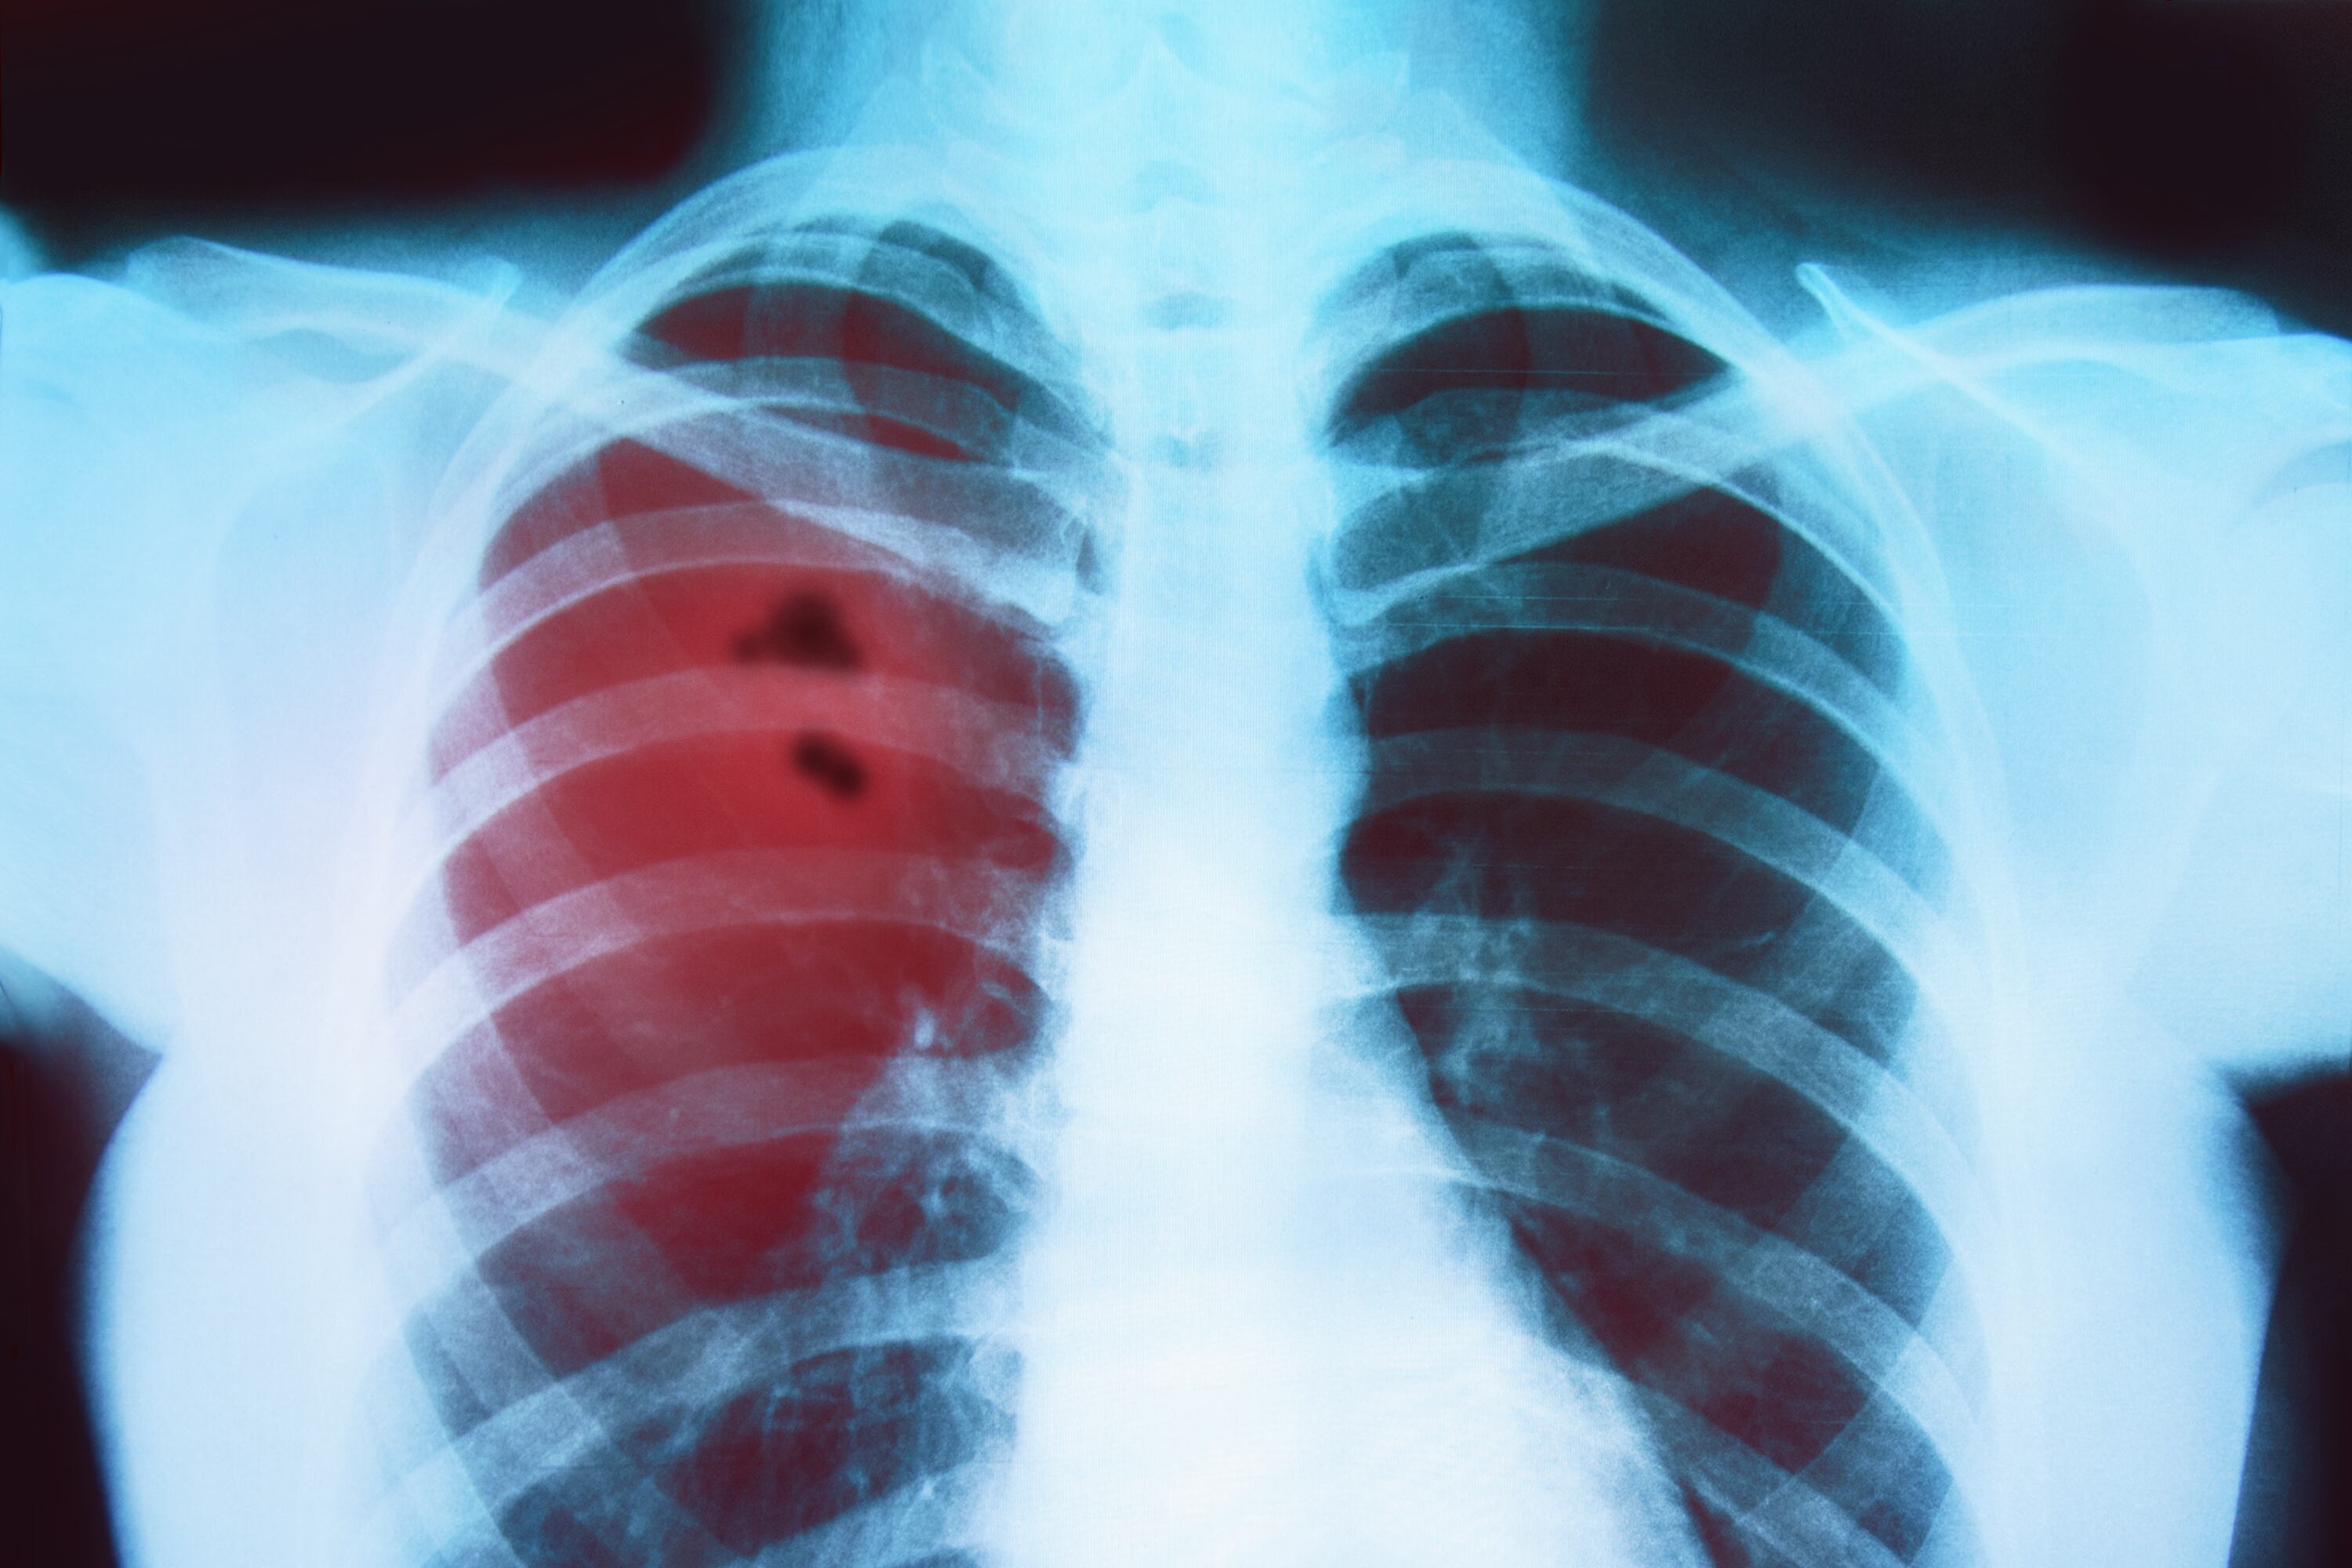

Cáncer de Pulmón. Foto: Getty Images / Fetrinka

Un estudio del Instituto Francis Crick, en el Reino Unido, reveló cómo la contaminación del aire causa cáncer de pulmón en personas que nunca han fumado. Según lo revelado, los datos explorados de más de 400.000 personas, se encontró que la exposición a partículas específicas de aire contaminado abre la puerta al crecimiento a células que son portadoras de mutaciones cancerígenas.

En diálogo con Sigue La W, Dra. Emilia Lim, co-autora del estudio, investigadora en el Instituto Francis Crick, explicó que debido a la alta contaminación que se tiene en todo el mundo, “todos estamos en riesgo” de padecer esta enfermedad.

“En la investigación de 400.000, el 15% de pacientes con cáncer de pulmón son no fumadores, y nos dimos cuenta que viene de la contaminación del aire”, dijo.

Asimismo, afirmó que se debe a que “hay una célula cancerígena que todos tenemos, pero eso no quiere decir que todos tengamos cáncer, sino que hay algo que la activa, y precisamente es la contaminación del aire”, enfatizó.

Explicó que la enfermedad que padecen los no fumadores tiene una gran diferencia con los fumadores, “hay una gran diferencia biológicamente, las mutaciones de los cánceres son muy distintas”.

Finalmente, comentó que generalmente en las zonas urbanas hay más contaminación, “digamos en en el centro de Londres, en las carreteras, cerca de zonas industriales y en zonas de incendios hay un nivel más alto, pero todos siempre estamos expuestos”.